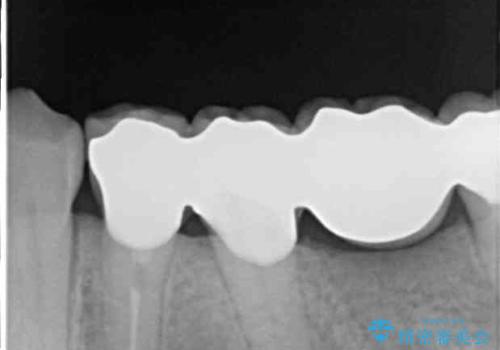

治療開始の日に欠損部も含めて仮歯が装着され、今までの不具合や不快感があっという間に改善されました。

抜歯部位の治癒を待つために時間がかかりましたが、来院回数は数回で済み、患者様には大変満足していただきました。